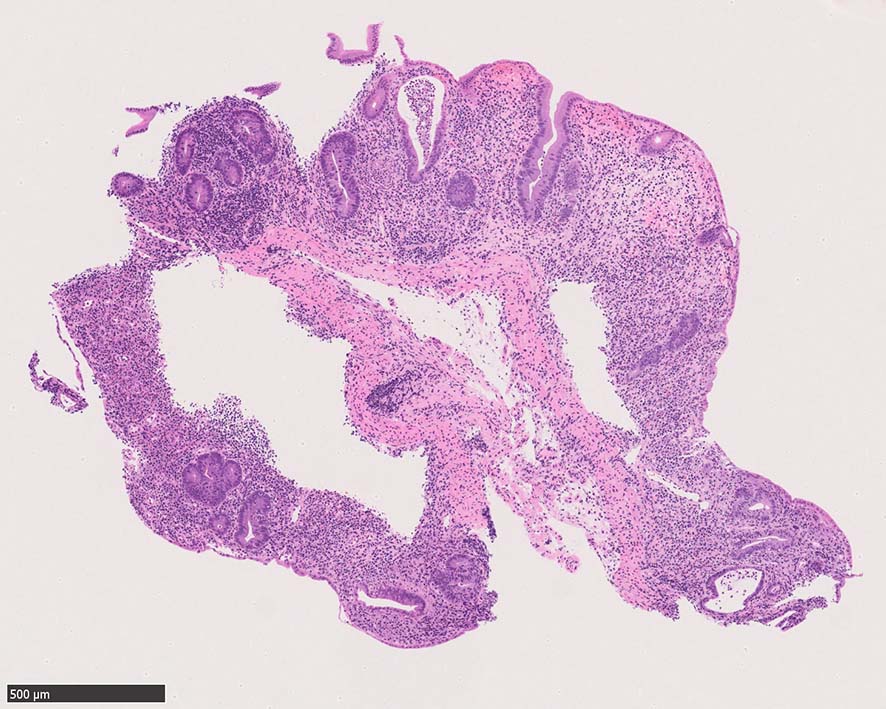

Case presentation

びらんを示す結腸粘膜. 陰窩はdeletion, 萎縮, distortionを呈する. 粘膜固有層には密な慢性炎症がみられ, 好酸球浸潤も多い.粘膜筋板へも炎症細胞浸潤が及ぶ.

UCのような, crypt abscess, cryptitisが認められる. 特徴的な所見として, apoptosis bodiesの増加が見られる.